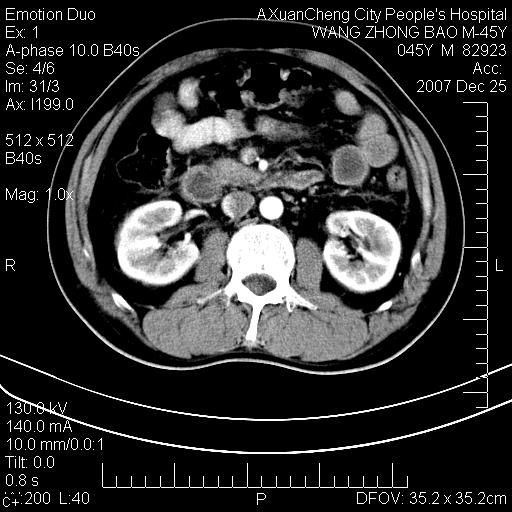

以下是引用qiuleiyu在2007-12-25 18:14:00的发言:[br]胰腺增大,周边渗出改变,肾前筋膜明显增厚,示少量积液.胆囊壁毛糙,周边少许渗出,胆总管壁厚,异常强化,然扩张不明显.结合病程急短;考虑;胆管炎,胆囊炎,胆源性胰腺炎可能大,请结合实验室检查及随访.

以下是引用lisihao在2007-12-25 14:23:00的发言:[br]急性水肿型胰腺炎[br]依据:1、胰腺弥漫性肿大,边缘稍毛糙;[br] 2、双侧肾周筋膜增厚,尤以左侧为甚(重要征象)[br] 3、双侧后胸膜增厚(刺激性炎症);[br] 4、结合病史,查血尿淀粉酶应该可以确诊。